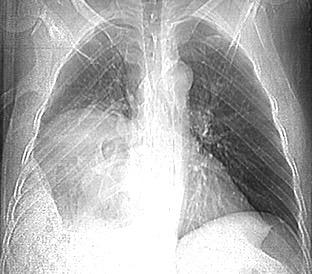

33. ENF. TORACOABDOMINAL. SEUDOQUISTE PANCREÁTICO

3 rasgos: Conexión entre mediastino y lesión pancreática. Derrame pleural Hallazgos de pancreatitis. Matsusue E et al.Three cases of mediastinal pancreatic pseudocysts. Acta Radiol Open. 2016 .